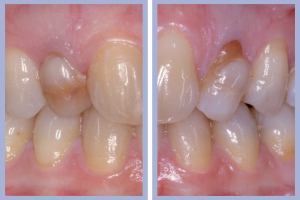

- Figg. 28a, b – Confronto tra inizio e fine trattamento

La valutazione clinica al momento della consegna dei manufatti e clinico-radiologica a 3 mesi dalla consegna manifestava una completa integrazione tissutale con eccellente recupero estetico e funzionale (Figg. 29-30).